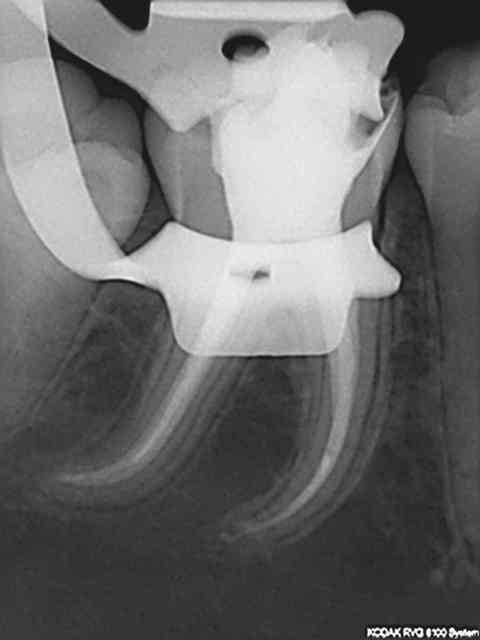

R29 uvltlt - Eugenol

R49 enunsh - Eugenol

R22 vkd0tr - Eugenol

R23 pmkimv - Eugenol

R26 gr1kkt - Eugenol

R34 w9wpow - Eugenol

Img 0052 dkvbyu - Eugenol

Leandro

28/02/2013 à 21h54

Joli travail!